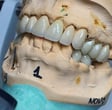

Coroa sobre Implante aparafusada em Modelo impresso. zirconia/cerâmica

Fase de produção laboratórial das coroas sobre dentes e implantes e facetas de porcelanas personalizadas

Em um bom laboratório, essas peças são confeccionadas com precisão, utilizando tecnologia avançada para garantir o ajuste perfeito e a estética desejada.